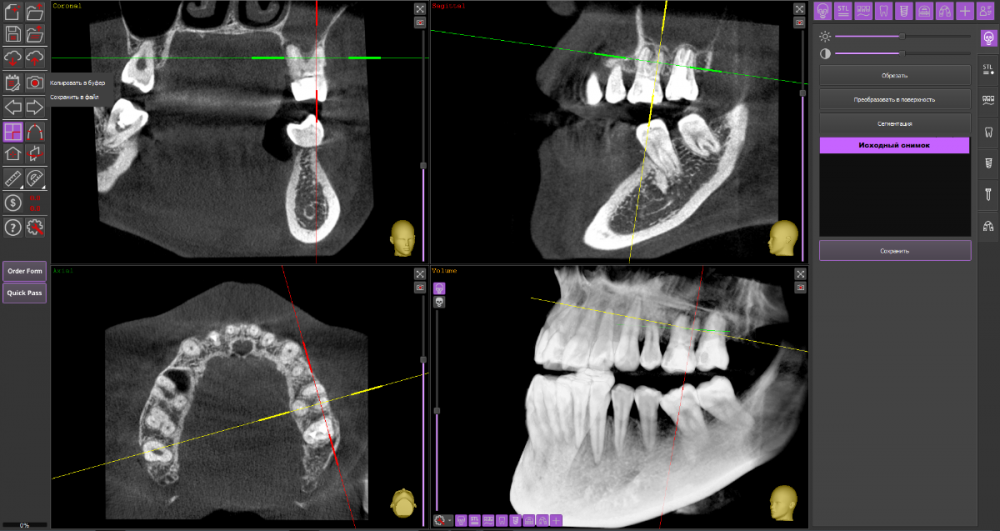

Киста 6,7 слева и гайморит

Гайморит: в начале декабре начала лечение гайморита, сделали прокол, вылился гной пропила антибиотики. ЛОР сказала идти лечить зубы

Зубы: лечение начала в конце декабря. на кт обнаружили кисту над 6,7 зубами слева. 7 зуб заходит в пазуху. Начали лечить 6, сказали что попробуют спасти, заложили лекарство на 2 недели. Также стоял ортодонтический имплантат рядом с 7 зубом, сказали что находится очень близко к корню зуба и пазухе. Имплант удалили.

КТ

Думаю, стоит пока попробовать консервативное лечение у стоматолога-терапевта.

26_2.thumb.png.4e2629dce11b9ee81966fd88dc76128c.png